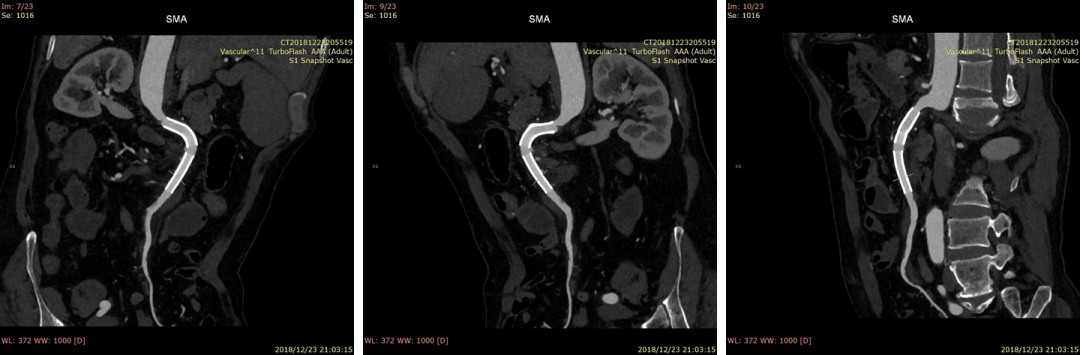

20181223CTA(术后6天)